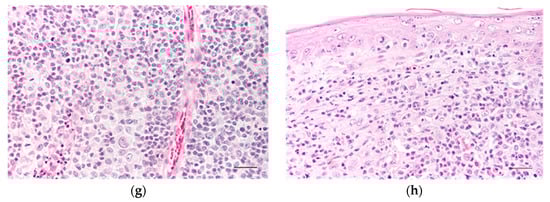

Group I (Figure 2a) tumours exhibited minimal lymphoid inflammatory infiltrate, which, when present, was confined to the periphery of the lesion. The neoplastic cells were uniform, with finely granular and acidophilic cytoplasm. Nuclei were round or oval, occasionally with nucleoli, and frequent mitotic figures ranged from 2 to 12 per high-power field (Figure 2b). Multinucleated cells were observed in one case. At the tumour periphery, the cells formed nests or cords with well-defined contours, sometimes separated by superficial oedema. Deeper in the tumour, the proliferation was solid, and the cells exhibited sparser cytoplasm with indistinct cellular contours. The tumour stroma was sparse. The epidermis was often hyperplastic, with pseudocarcinomatous hyperplasia in more than half of the cases. Ulceration was present in most cases (n = 13; 86.7%), typically small in size. Necrosis, when present (n = 6; 40%), was generally sparse and located at the periphery of the tumour.

Figure 2.

Light microscopy images of canine cutaneous histiocytoma. (a) Canine cutaneous histiocytoma from histological Group I; the tumour cells occupy the superficial dermis. Lymphoid infiltrate at the periphery of the lesion. Scale bar = 300 μm; (b) detail of the previous image. Scale bar = 30 μm. (c) Canine cutaneous histiocytoma from histological Group II; the lymphoid infiltrate forms follicles at the periphery of the tumour. Scale bar = 300 μm. (d) Canine cutaneous histiocytoma from histological Group III; the lymphoid infiltrate is abundant in the centre and periphery of the tumour. Scale bar = 300 μm; (e) detail of the previous image. Scale bar = 60 μm. (f) Canine cutaneous histiocytoma from histological Group IV; the lymphoid infiltrate is abundant and reaches the surface of the tumour. Tumour cells are scarce. Scale bar = 60 μm; (g) CCH from Group IV; the lymphoid infiltrate is more abundant than the tumour cells. Note the polygonal shape of the cells. Scale bar = 30 μm; (h) CCH from Group IV, showing scarce tumour cells, abundant lymphocytes, and fibroblast proliferation at the dermo-epidermal junction. Scale bar = 60 μm.

Neoplasms in Group II (Figure 2c) displayed moderate lymphoid infiltration at the tumour’s periphery, organised into nodular formations, sometimes with an apparent organoid structure centred by a blood vessel. The morphology of the neoplastic cells was identical to that described in the previous group, with multinucleated cells observed in three cases. The epidermis was hyperplastic in 10 cases (66.6%), showing irregular or pseudocarcinomatous hyperplasia or extensively ulcerated (n = 5; 33.3%). Ulceration was present in almost all cases (n = 14; 93.3%), with a predominance of extensive ulcers (n = 8; 53.3%). Necrosis was observed in 66.7% (n = 10) of the lesions, mainly sparse to moderate at the basolateral periphery.

Tumours in Group III (Figure 2d,e) exhibited abundant lymphoid infiltration, capable of forming nodular structures both at the periphery and the centre of the tumour. Neoplastic cells constituted a smaller proportion of the total cell population. The nuclei were less dense, and the nucleolus was more frequently visible. The cytoplasm was occasionally vacuolated, and cells sometimes appeared polygonal. Solid areas seen in Groups I and II tumours were observed at the centre and surface of the tumour but were smaller, located amid intense inflammatory infiltration. The stroma was scarce, except in seven cases (16.7%). Sometimes, fibroblast proliferation was observed at the apical surface of the lesion, separating it from the epidermis, which was normal in these areas. The epidermis was generally hyperplastic (n = 24; 57.2%) and frequently ulcerated (n = 37; 88.1%), with intense infiltration by neutrophils, reaching deep areas of the tumour in two cases. In 14 cases (33.3%), the ulcer covered the entire surface of the neoplasm. Necrosis was evident, moderate to extensive (n = 25; 59.6%), both in the centre and at the base of the tumour. Multinucleated cells were observed in six cases (14.3%).

Group IV included tumours with very intense inflammatory infiltration (Figure 2f). This infiltration was observed from the tumour margins to the dermo-epidermal junction, occupying an area larger than the neoplastic cells (Figure 2g). The neoplastic cells, with well-defined cellular contours, appeared individualised and not in solid areas located from the surface into the lesion. Some cells, polygonal in shape, had pale cytoplasm and a pleomorphic, round to oval, and indented nucleus. In contrast, others appeared degenerated with eosinophilic cytoplasm and a small, eccentric “C-shaped” nucleus. Multinucleated cells, primarily binucleated, were frequent. The tumour stroma was moderate. Ulceration was present in almost all cases (n = 21; 90.5%), and the epidermis, when present, was generally hyperplastic. In two cases (9.5%), the epidermis appeared normal. In certain areas, the epidermal ridges were non-existent, and a single layer of cells represented the different epidermis layers. Fibrous tissue separated the epidermis from the remaining tumour (Figure 2h). Areas of necrosis observed in 50.0% (n = 10) of the tumours were moderate or extensive. In cases where necrosis was not evident, areas of fibrosis were observed among the inflammatory infiltrate.